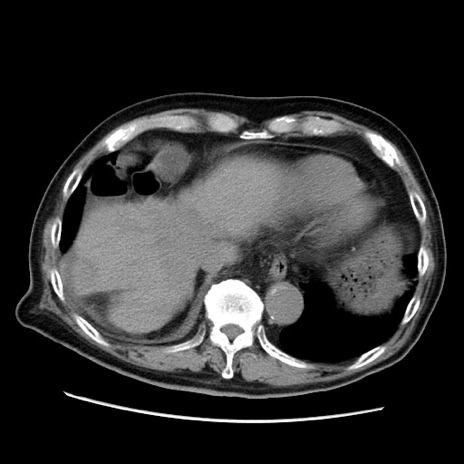

症例21(横断像)

【症例】70歳代男性

【主訴】腹痛

【現病歴】肝硬変・肝細胞癌にてかかりつけの方。約9時間前に食後より腹痛出現。症状が徐々に増悪し、嘔吐出現したため来院。

【既往歴】肝硬変、肝細胞癌(RFA、TACE後)

【身体所見】意識清明、表情苦悶様、BT 36℃、BP 129/78mmHg、P 88bpm、SpO2 97%(RA)、右上腹部から心窩部にかけて圧痛あり、反跳痛なし、筋性防御あり。

【データ】WBC 5800、CRP 0.16